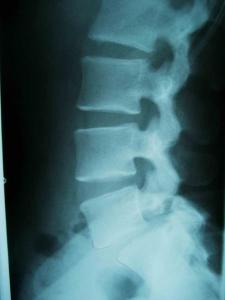

人体的老化是不可抗拒的自然规律,随着年龄的增长,腰椎由于运动磨损不可避免地会出现退行性改变,绝大部分60岁以上的正常人拍片时均可发现腰椎的骨刺形成,椎间隙狭窄等退变老化现象。

6.X片显示椎体有骨赘增生,椎间隙狭窄。